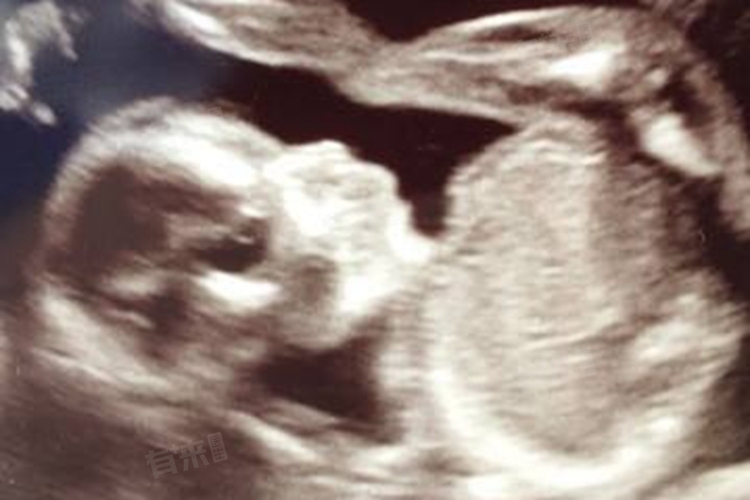

- 孕20-24周的大排畸检查,是孕期非常重要的一次B超检查。此时胎儿各器官已发育成形,通过B超可系统筛查胎儿是否存在严重的结构畸形,如颅脑、心脏、脊柱、四肢等部位的发育异常。此次检查能够为孕妇及家属提供重要的决策依据,若发现严重畸形,可及时采取相应措施。